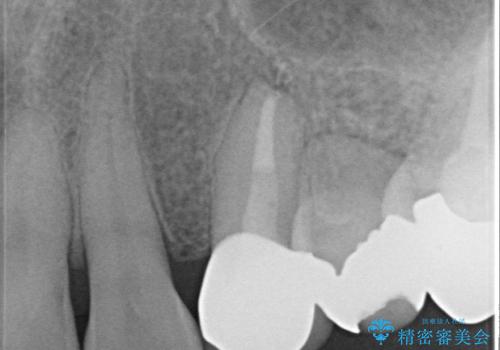

オールセラミッククラウン 再根管治療後の補綴

- 他院にて左上3番の被せ物を勧められたが、根管治療からやり直したいと当院にいらっしゃった方の症例です。

再根管治療後、オールセラミッククラウンによる補綴を行いました。